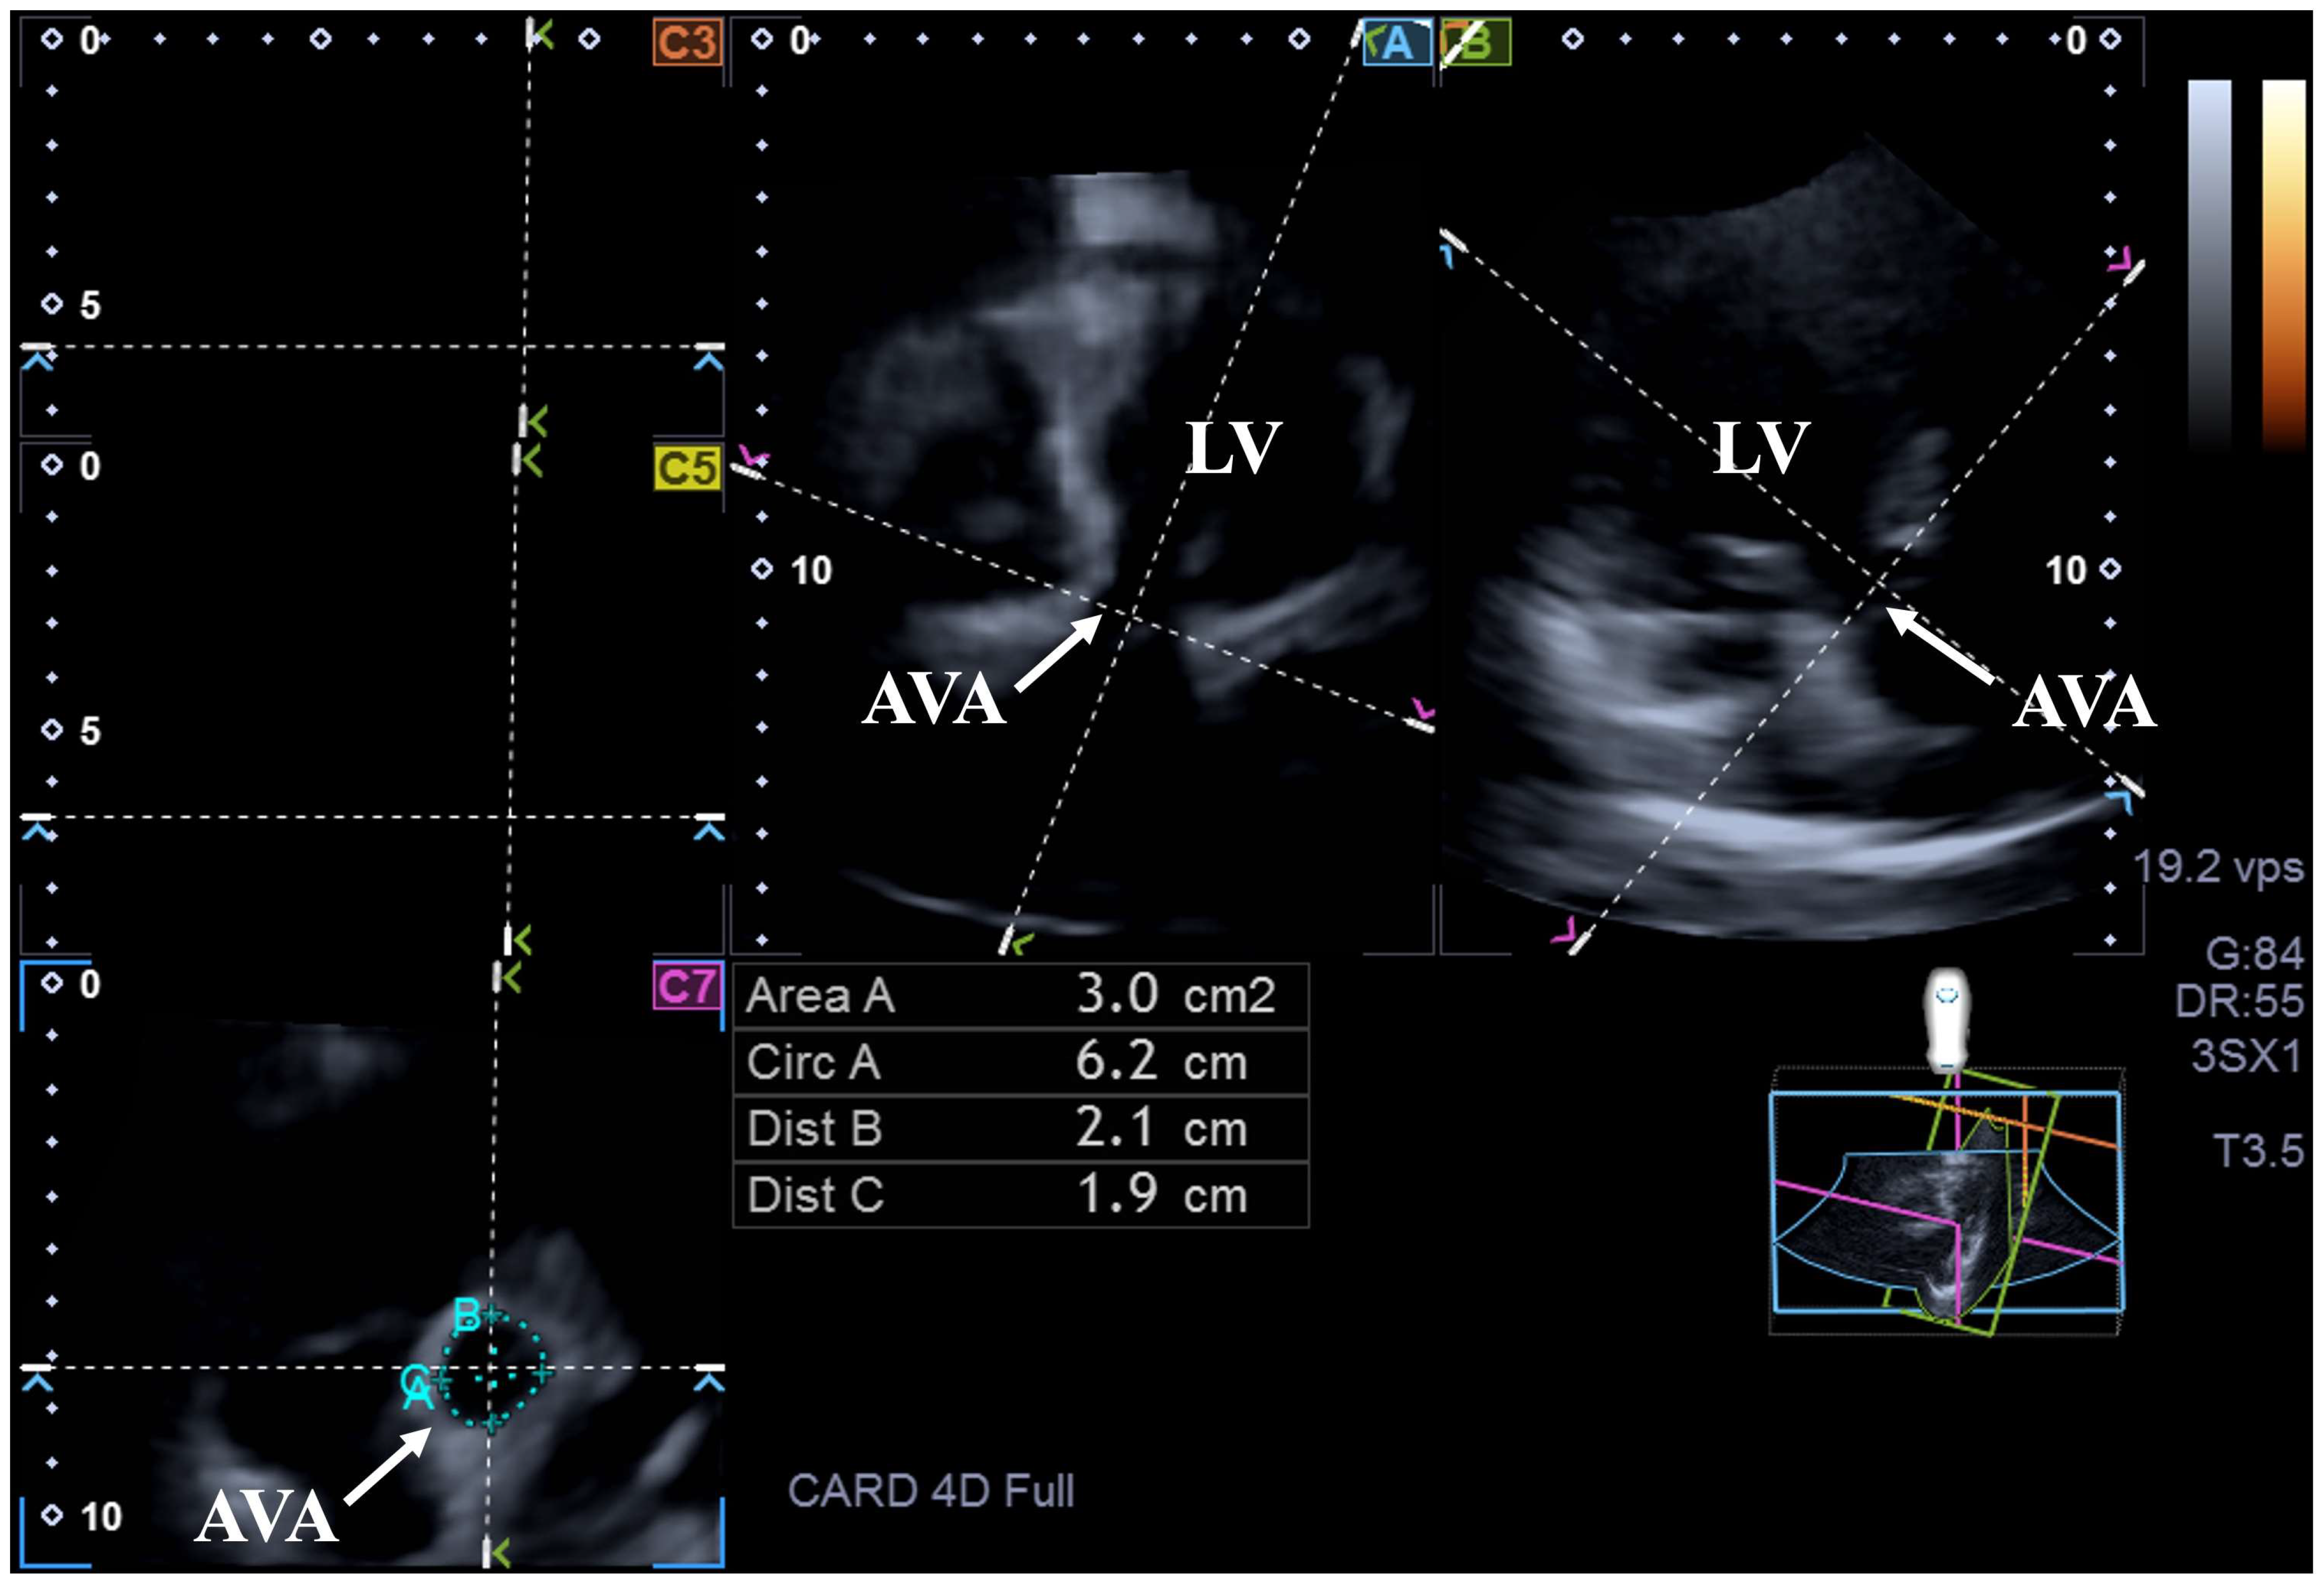

2. Materials and Methods

3. Results